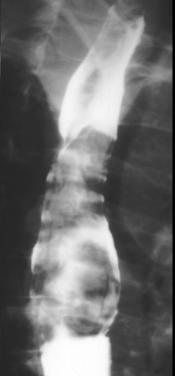

5 Leiomyome

: Le plus frequence des tumeurs begnines et le plus

souvent 2/3 inferieure de oesophage . Image TOGD baryte

et TDM est une masse unique , homogene polylobee et

pseudocapsule avec contour bien limite . Signe clinique

est : douleur thoracique , et dysphagie

Image TOGD de leiomyoma du

portion inferieure de oesophage . Image laculaire

intramurale: bord net , lisse a inferieure de

oesophge |